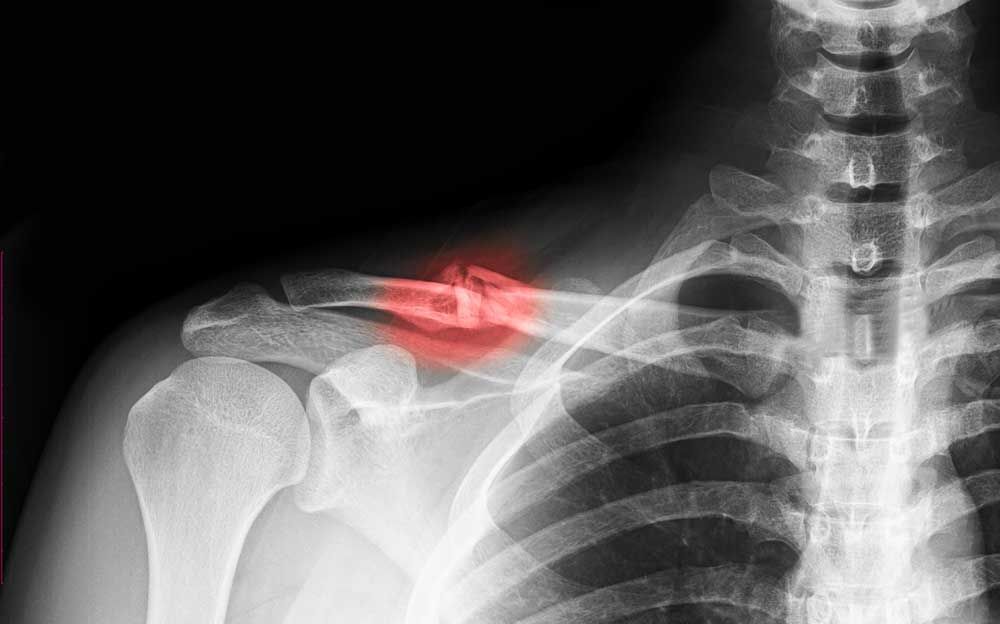

OMUZ CERRAHİSİ ve OMUZ HASTALIKLARI